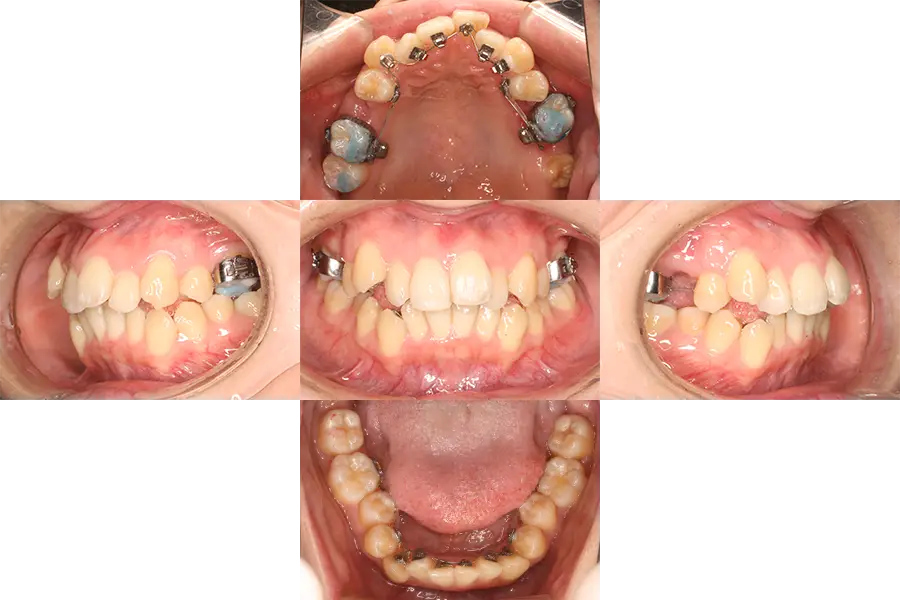

治療開始時は、上の前歯が口を閉じられないほど出ており、患者様ご自身も口元の突出感を大変気にされておりました。

また、上下前歯部の凸凹(ガチャ歯)も重度であり、患者様とご相談した結果、小臼歯を計4本抜いて凸凹を改善させるだけでなく、上の歯列全体を後方移動させる(I-stationというアンカースクリューが必要)ことで、上顎前突や口元の突出感(口ぼこ)、口唇閉鎖不全(口のとじづらさ)を改善させることとなりました。